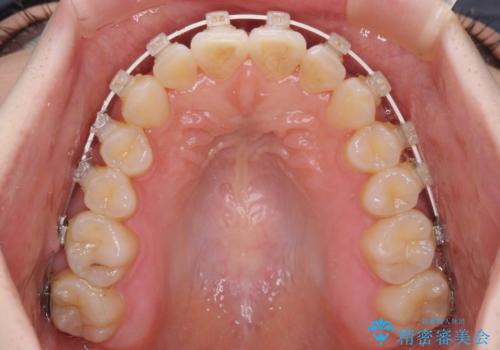

半年もせずにインビザラインを全く使用することができなくなってしまったので、治療開始から1年ほどでワイヤー矯正へ変更することとなりました。

ワイヤー矯正へ変更してからはあっという間に治療が進み、1年弱で終えることができました。